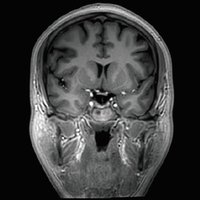

Der Vantage Galan 3T von Canon Medical Systems bietet Ihnen und Ihren Patienten eine neuartige Erfahrung in der Magnetresonanztomographie. Der Vantage Galan 3T legt sein Augenmerk auf das positive Patientenerlebnis, eine hohe Bildqualität und einfache klinische Arbeitsabläufe.

Auch das Patientenwohl kommt bei dem Vantage Galan 3T nicht zu kurz. Der kurze Magnet wird ergänzt durch eine 71cm weite Patientenöffnung. Ein helles und modernes Design lässt den MRT weniger bedrohlich wirken. Die Pianissimo Technik verringert die Geräuschbelastung während der Untersuchung signifikant und MR Theater trägt durch visuelle Eindrücke zur Entspannung des Patienten bei.